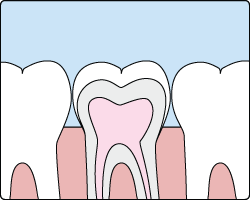

Sealants are a thin protective coating that adheres to the chewing surface of your back teeth. There is no substitute for brushing and flossing, but they can keep cavities from forming and may even stop early stages of decay from becoming a full-blown cavity.

The whole purpose of a sealant is to protect vulnerable teeth surfaces while the teeth are newly erupting. Studies have claimed that good retention is seen up to five years after their placement. The resin-based sealants showed the best retention rates.